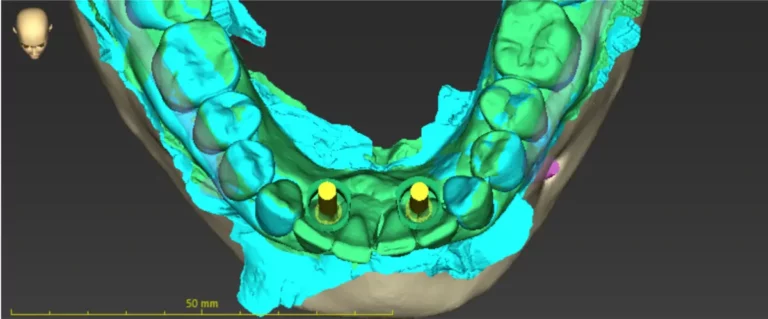

Mediante un TAC dental en 3D y un escáner intraoral, analizamos la anatomía del paciente y planificamos la posición exacta de los implantes en función de la planificación protésica.

A partir de esta planificación se fabrica una férula quirúrgica personalizada que guía la colocación de los implantes durante la intervención con una precisión milimétrica.

Mediante software especializado planificamos la posición ideal de los implantes teniendo en cuenta la futura prótesis dental.

Esto permite diseñar el tratamiento con máxima precisión antes de la cirugía.